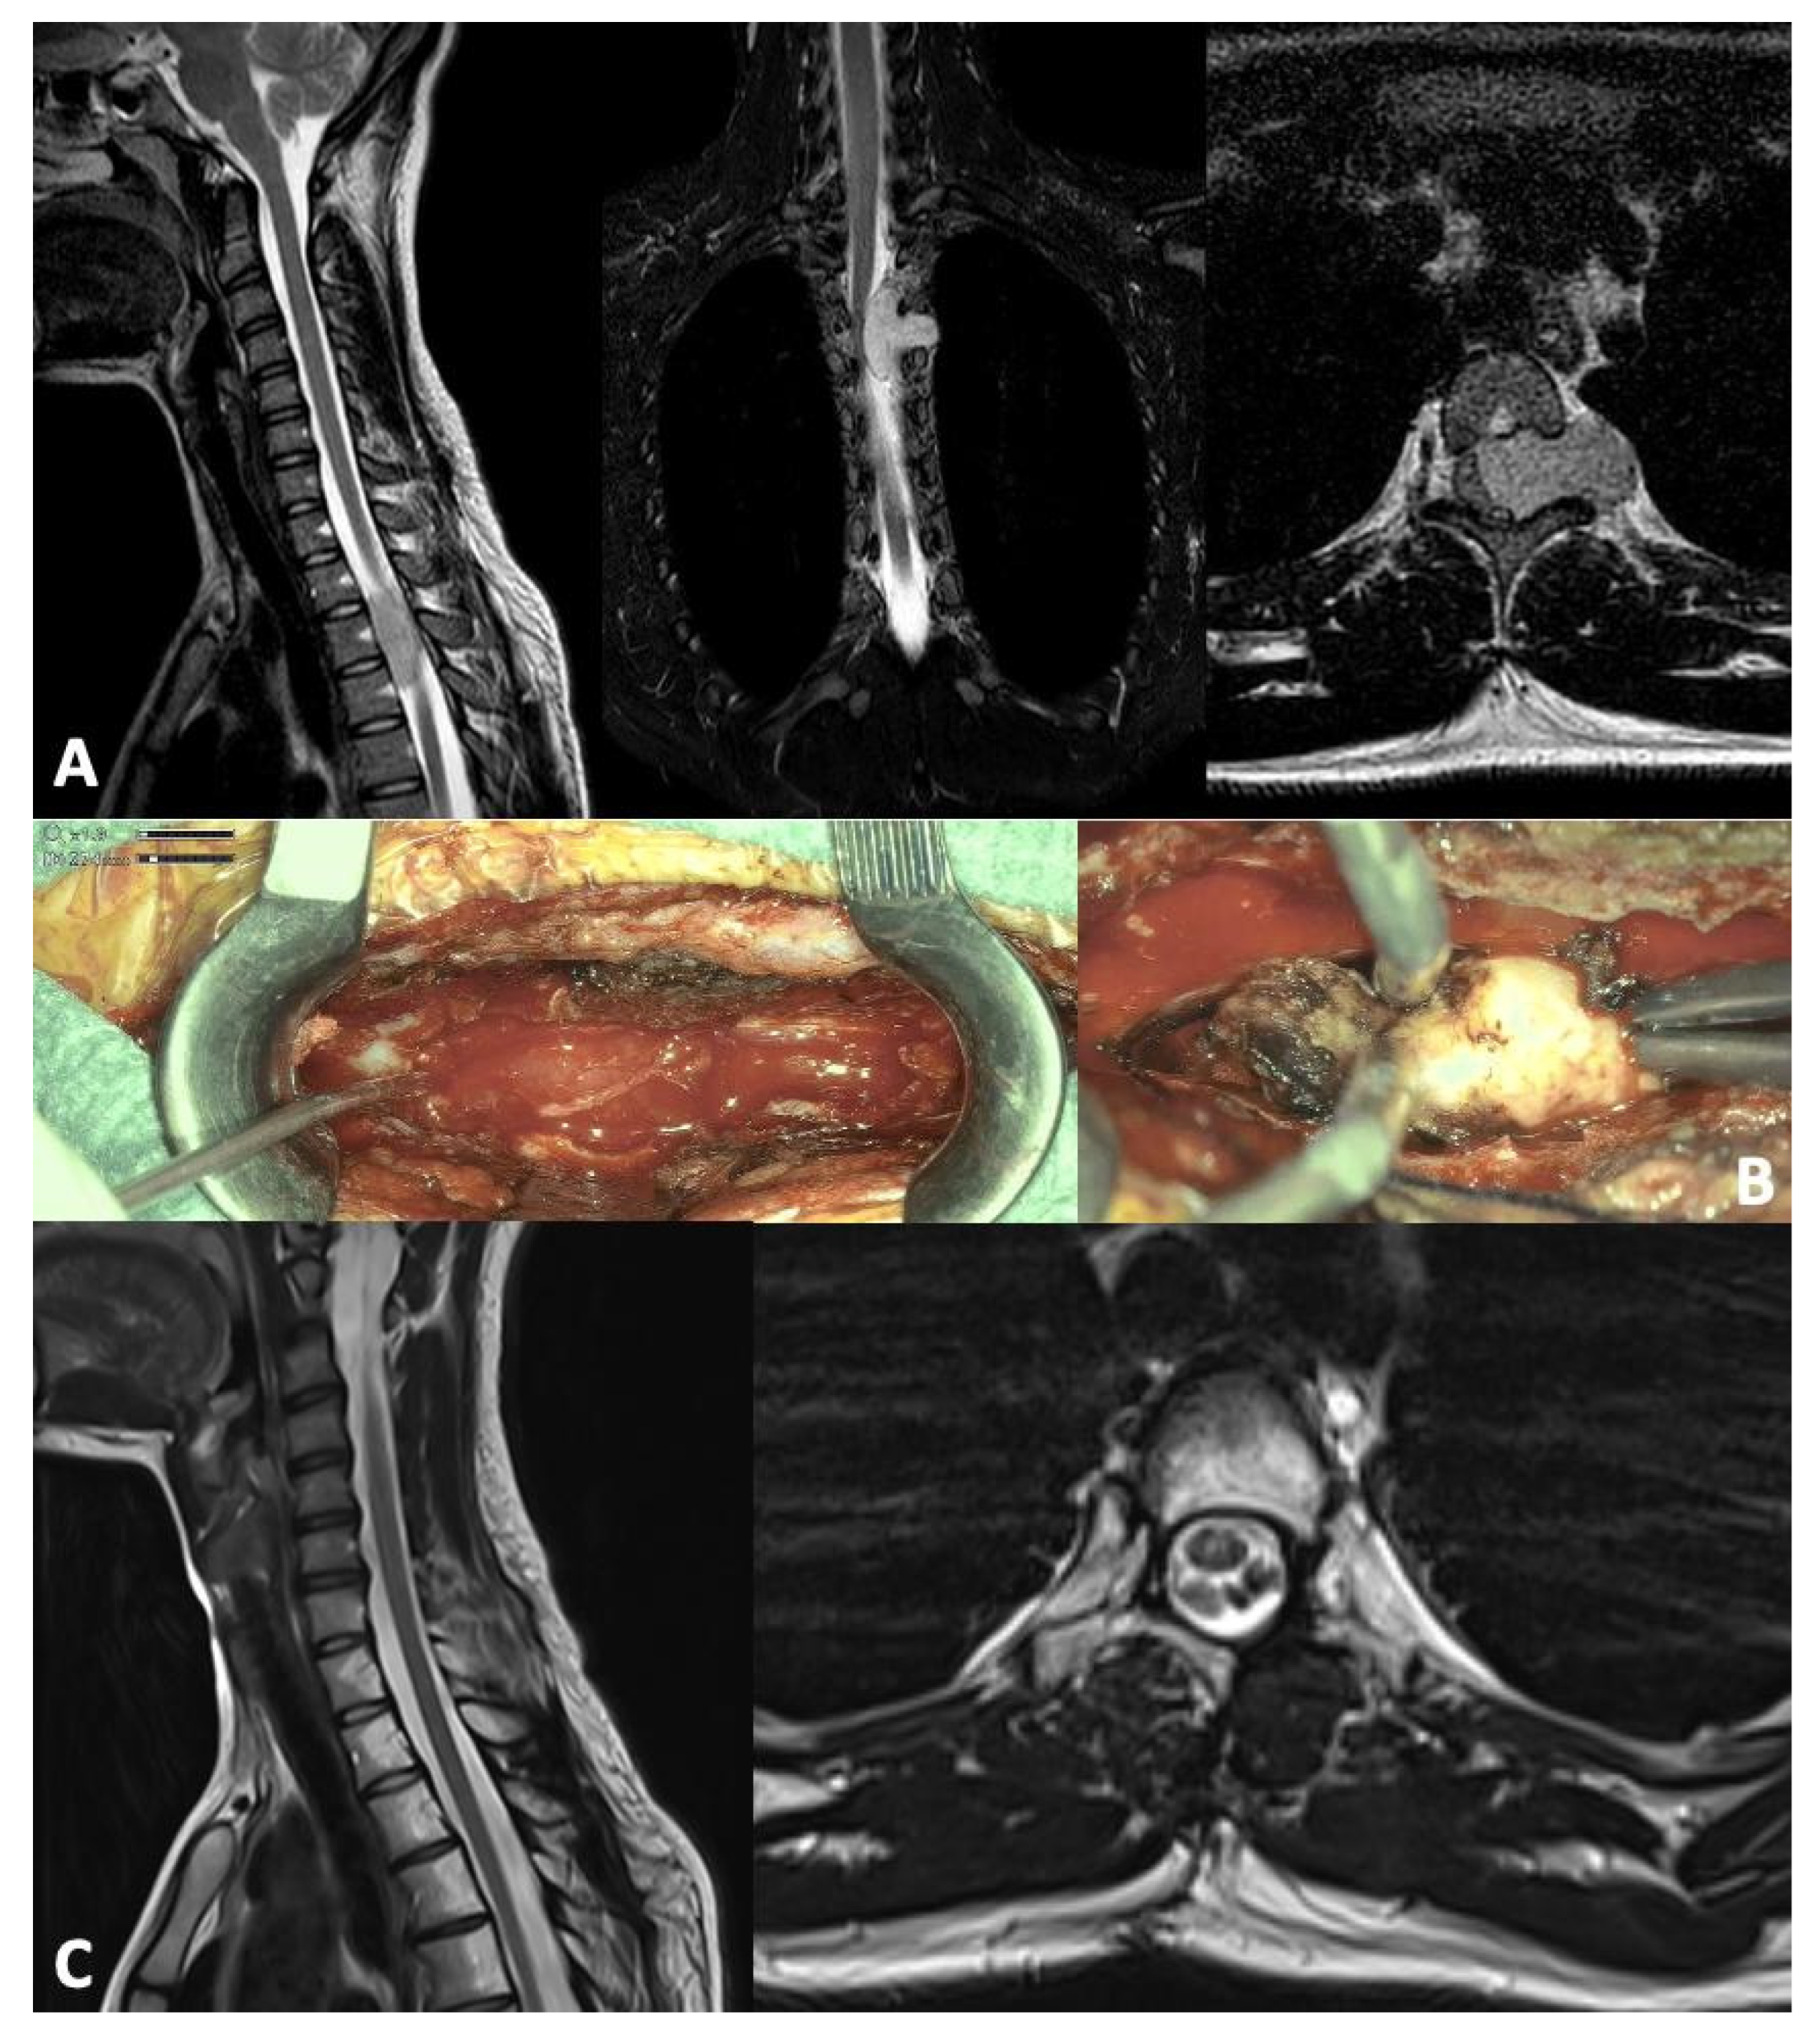

| Trezza et al. 2025 | Case report | 1 (17 y.o./F) | Left interscapular unresponsive pain | Extramedullary intradural lesion D3–D4; mild myelopathy and cord compression | GTR + RT (protons; 50.4 Gy) | Disease free at 24 months | Case report |